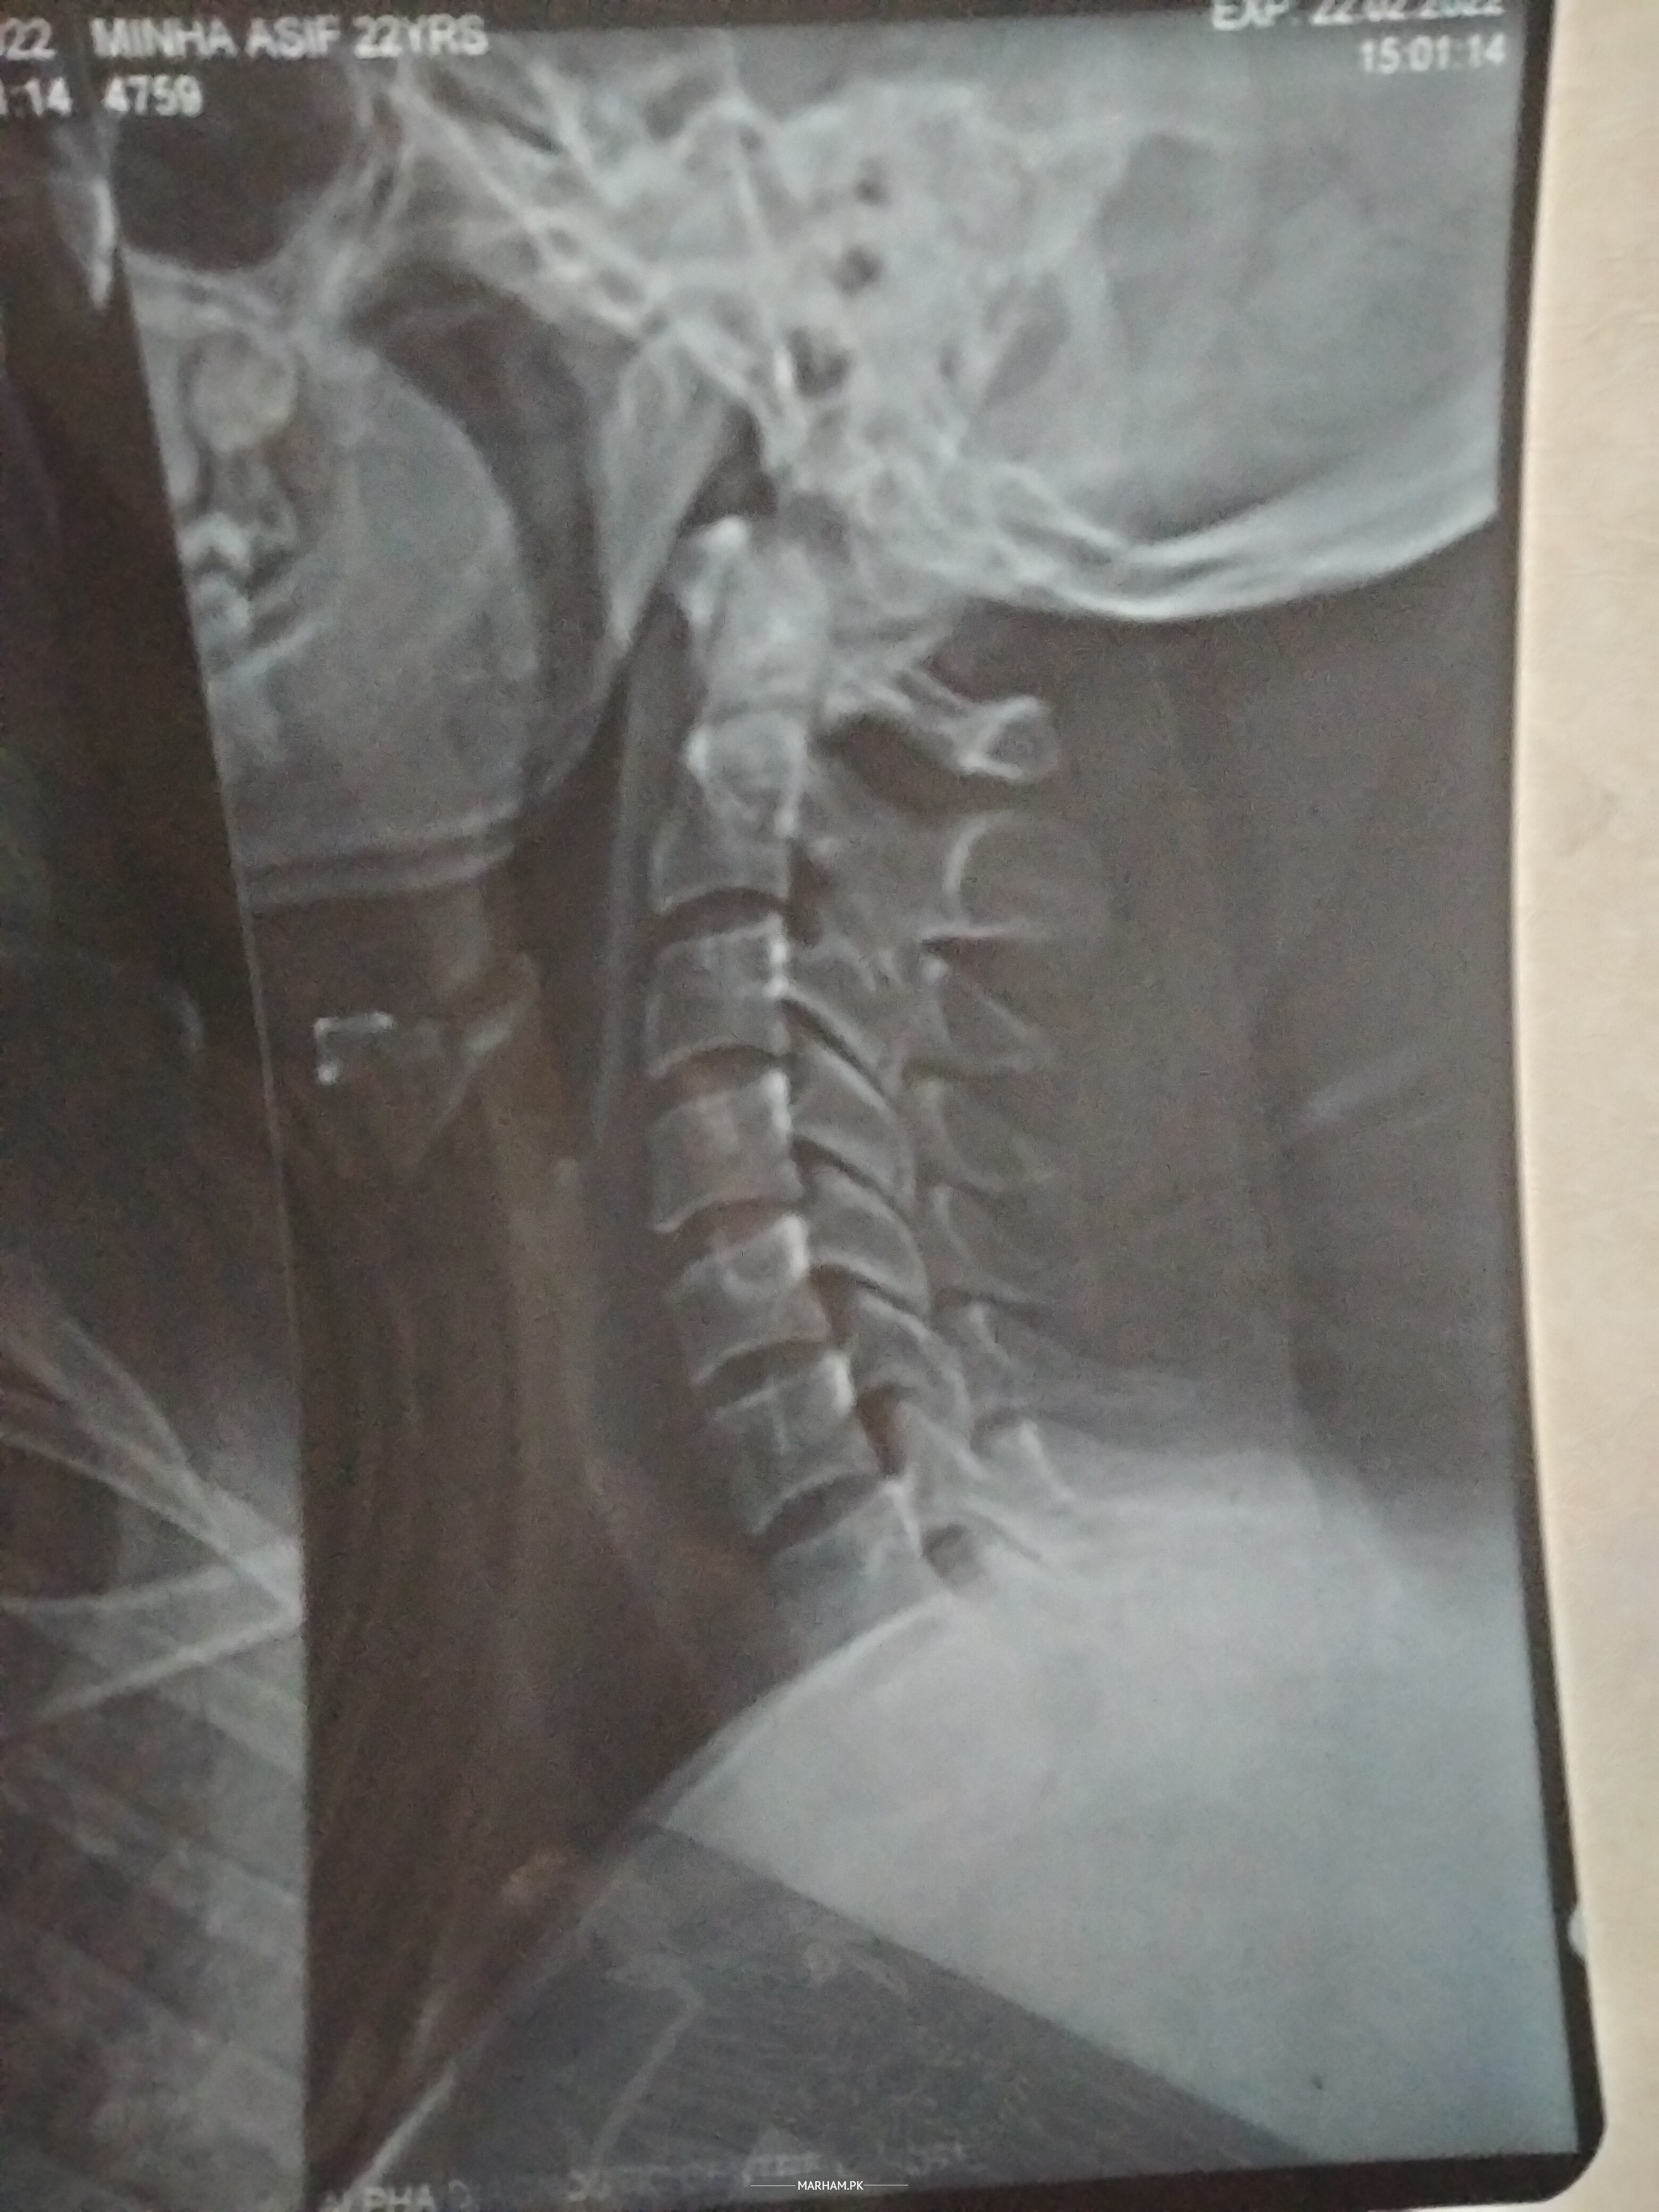

cervical xray attach kia hy

cervical xray

Member of Marham-Forum